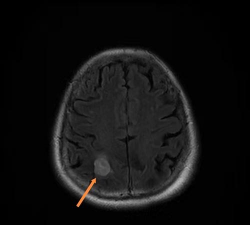

白内障

白内障是一种晶状体混浊的疾病,会影响视力,最终导致完全失明。

在小马驹中,白内障是最常见的先天性眼部缺陷。它们是由比利时马和摩根马继承的。白内障通常发生在双眼。当这些白内障干扰健康小马的视力时,在大多数情况下,手术后进行局部治疗是成功的。

在成年马中,大多数白内障是由于与马复发性葡萄膜炎相关的前葡萄膜炎症引起的。20岁以上的马可能会患上所谓的老年性白内障,影响视力。手术摘除晶状体是唯一可行的最终治疗方法。